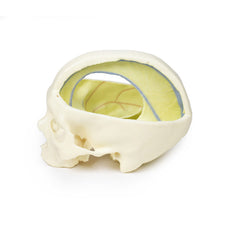

3D Printed Sagittal Section of Head with Infratemporal Fossa Dissection

This 3D model provides a combined midsagittal section through the head and

superior neck coupled with a deep dissection into the infratemporal fossa

region and superficial dissection of the scalp.

In the preserved midsagittal section there is preservation of the endocranial

contents, the nasal and oral cavities, and the pharynx to the level of the

laryngeal cartilages. The nasal cavity is preserved nearly intact, except for a

small window excised into the middle nasal concha to expose the ethmoid

air cells. A very large sphenoid sinus exists in the individual just superior

to the torus of the auditory tube in the nasopharynx. The oral cavity and

laryngopharynx are undissected, with the larynx only preserve just distal to the

level of the arytenoid cartilages and not including a clear set of vocal folds.

Within the endocranial cavity, the sectioned brain is slightly off the midagittal

plane, such that neither the superior sagittal sinus nor the third ventricle are

clearly defined - but the lateral ventricle is open and part of the fourth ventricle

is preserved between the pons and cerebellum. The gyri and sulci of the

cerebrum are not well separated, but the cingulate gyrus and corpus callosum

can be separated. Cross-sectioned views of the optic tract, pituitary gland,

superior and inferior colliculi, superior cerebellar peduncle, and transition

between the medulla oblongata and spinal cord are all visible. The tentorium

cerebelli and confluence/transverse sinus is positioned between the

cerebellar hemisphere and occipital lobe. Small portions of the posterior

inferior cerebellar artery, vertebral arteries, basilar artery, and posterior

cerebral and anterior cerebral arteries are visible in section.